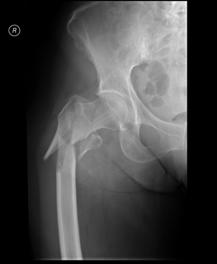

Luxatie de sold stang Luxatie de sold stang

Fractura

de cap femural Fractura de cap femural

Aspect

CT

de cap femural Fractura subcapitala cu usoara deplasare

Aspect CT